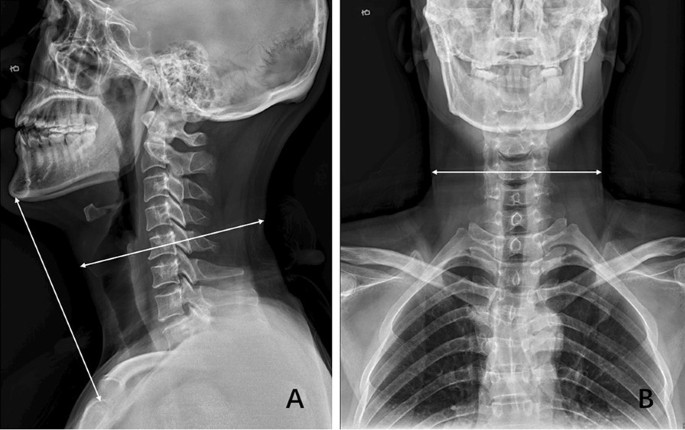

The mean time of surgery in this study was 120.3 min which was chosen as the cut-off. Operation time longer than 120 min or intraoperative blood loss equal to or greater than 200 ml was considered as a high-difficult surgery. Otherwise, it was defined as low-difficulty surgery. Examined radiological parameters included high signal intensity of spinal cord on T2-weighted images, OPLL, sagittal cervical circumference, coronal cervical circumference, cervical length, anteroposterior diameter of the spinal canal, the shortest diameter of the spinal canal, and spinal canal occupational ratio. Sagittal and coronal cervical circumferences were defined as the distance between the intersection of the line parallel to the endplate through the midpoint of C5 and soft tissue shadow (Fig. 1). Cervical length was measured as the distance between the sternum and gnathion on the lateral radiograph (Fig. 1a). The anteroposterior and shortest diameter of the spinal canal were measured at the most compressed level using standard picture archiving and communication system (PACS). Anteroposterior diameter was the distance between the posterior edge of the vertebral body and spinal canal while the shortest diameter was defined as the distance between the posterior edge of the compression and spinal canal. The following formula was used to calculate the spinal canal occupational ratio: spinal canal occupational ratio = (anteroposterior diameter-shortest diameter)/anteroposterior diameter (Fig. 2).

Sagittal radiograph showing that the cervical length was measured as the distance between the sternum and gnathion. Sagittal and coronal cervical circumferences were defined as the distance between the intersection of the line parallel to the endplate through the midpoint of C5 and soft tissue shadow